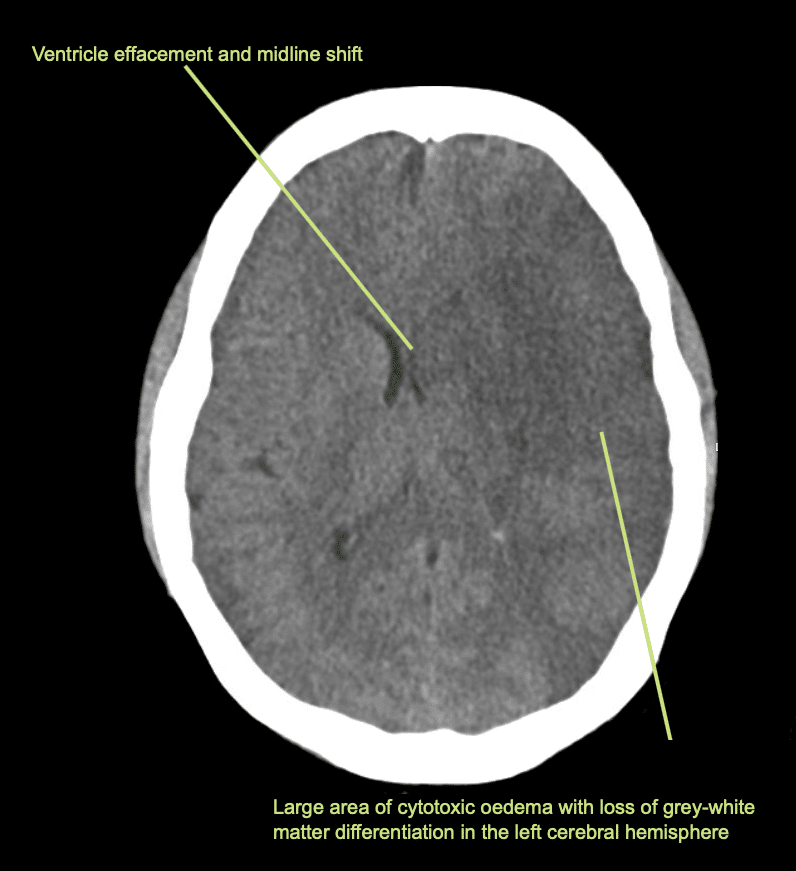

Descrivi e interpreta la TAC

Interpretazione della TAC